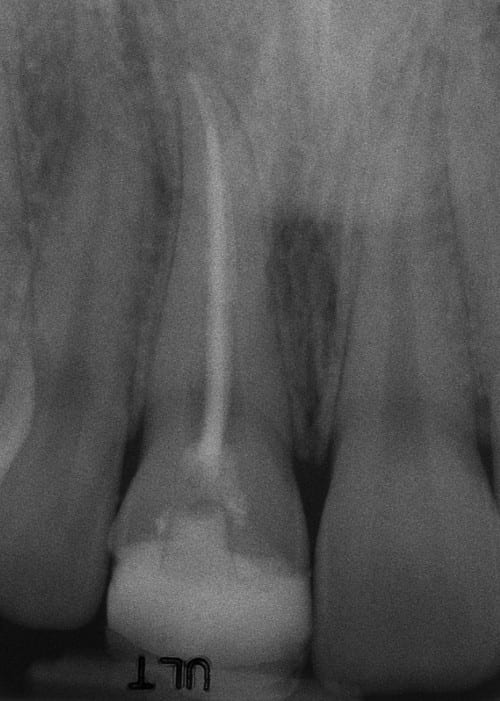

Before:Â Tooth #8 (upper right central incisor) has a history of trauma and root canal therapy. Re-treatment of the root canal filling was required.